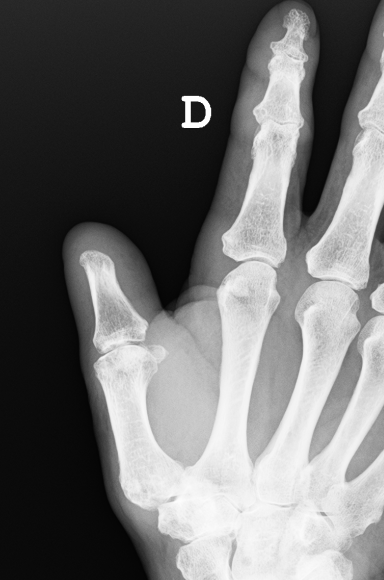

Caso clínico: Varón de unos 70 años que sufre accidente doméstico al quedar atrapado su dedo pulgar en la sierra que estaba usando. Acude a Urgencias.

Amputación a nivel de interfalángica con gran afectación de partes blandas y colgajos de piel desvitalizados. Se muestran las radiografías.

Radiografía de control. En la operación se extirpó el cartílago de la falange y se remodeló para permitir buena cobertura de partes blandas.

Radiografía a los tres meses y resultado final.